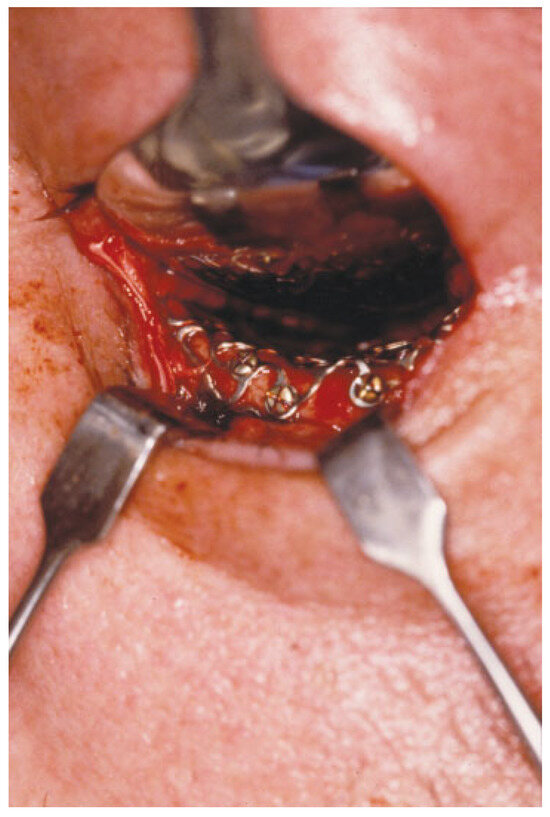

| Transconjunctival Incision with lateral canthotomy | 40/43 |

| Subciliary Incision | 3/43 |